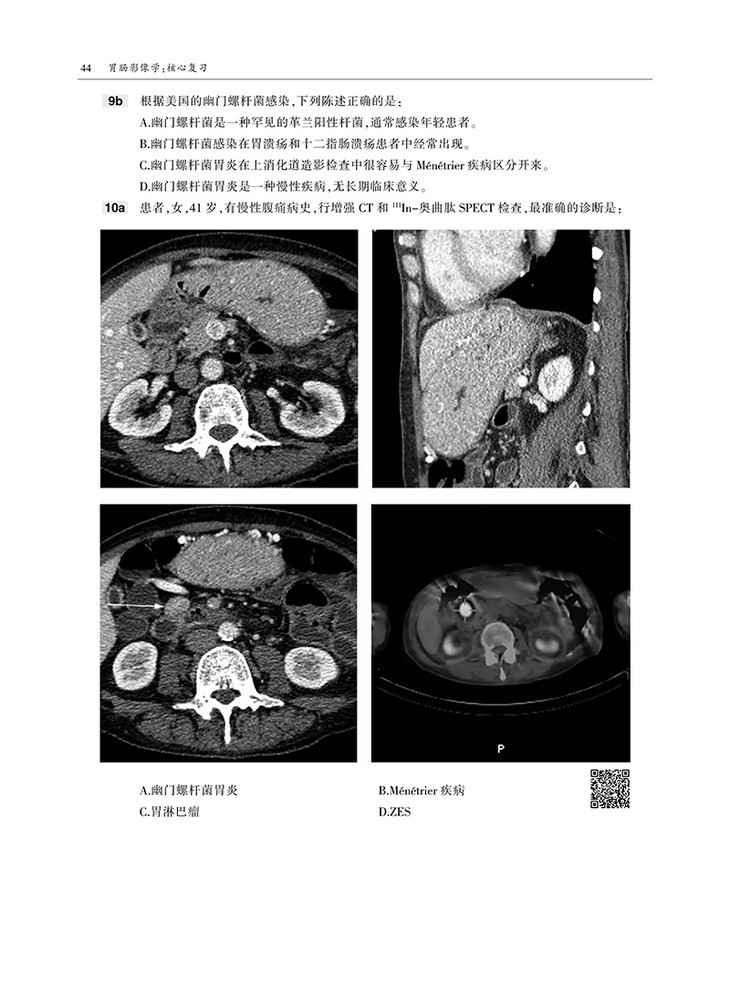

本书内容采用问答体例,首先给出患者病史和影像图片,然后列出问题和选项,便于读者独立思考,选择答案。各章末附有选择题答案和解析,正确选项和错误选项均有详细的注释,有助于读者加深理解和记忆。

囊括数百幅高清图像,直观显示病变的形态与特点等。